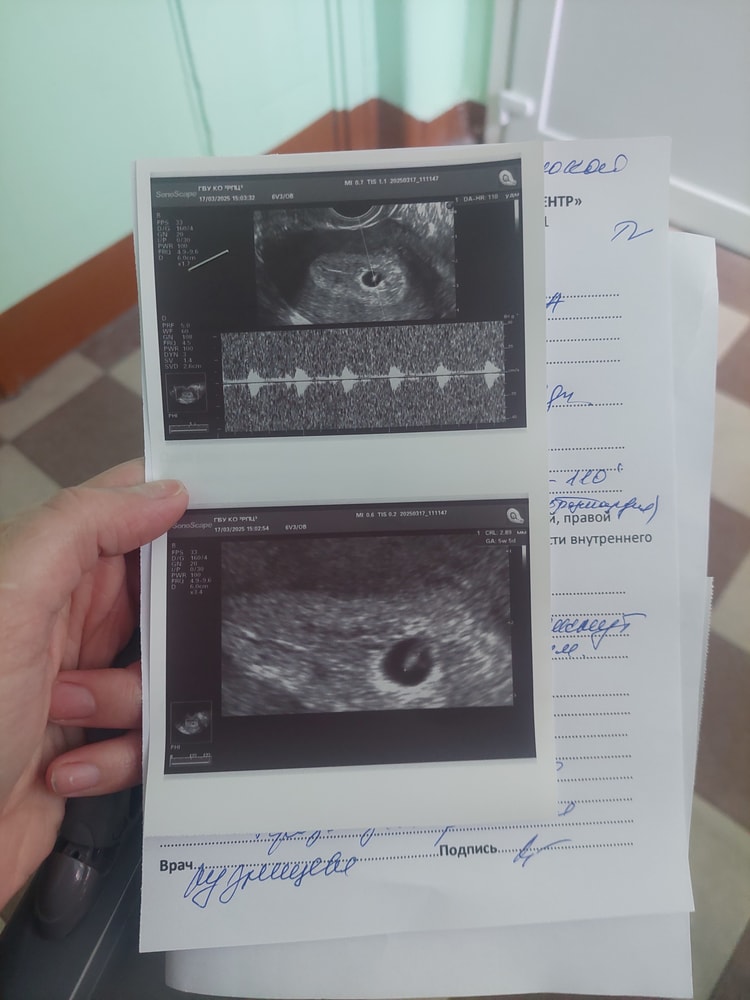

В пятницу 28 числа выписали с отслойкой и чуть почуть мазало с понедельника по узи все было хорошо ктр 7.4 мм сердцебиение + пя 12 мм , отслойка 10×8мм

03.03 хгч 130

10.03 хгч 2192

12.03 хгч 2362

12.03 узи (плодное яйцо 8 мм, жёлтый мешочек 3мм)

16.03 хгч 2234 (падает)

Поехала сегод

Плодное яйцо 8 мм , желточный мешок 3 мм . Эмбриона пока невидно, врач сказала хгч больше не сдавать а прийти через неделю .